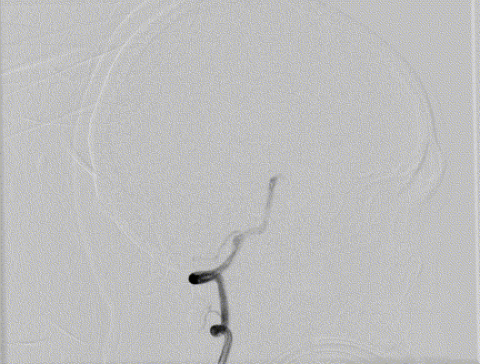

造影显示左侧椎动脉非优势侧

(5F造影导管即造成造影剂的滞留)

右侧椎动脉造影证实V4段夹层动脉瘤

(可见内膜瓣/瘤内造影剂滞留)